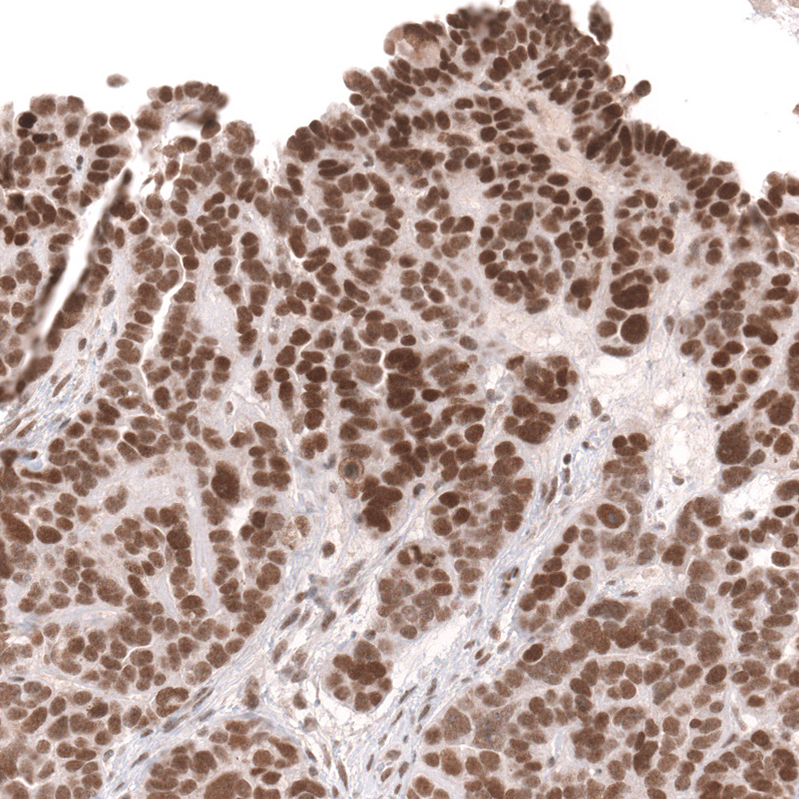

Immunohistochemical staining of human cerebral cortex shows strong nuclear positivity in neurons.